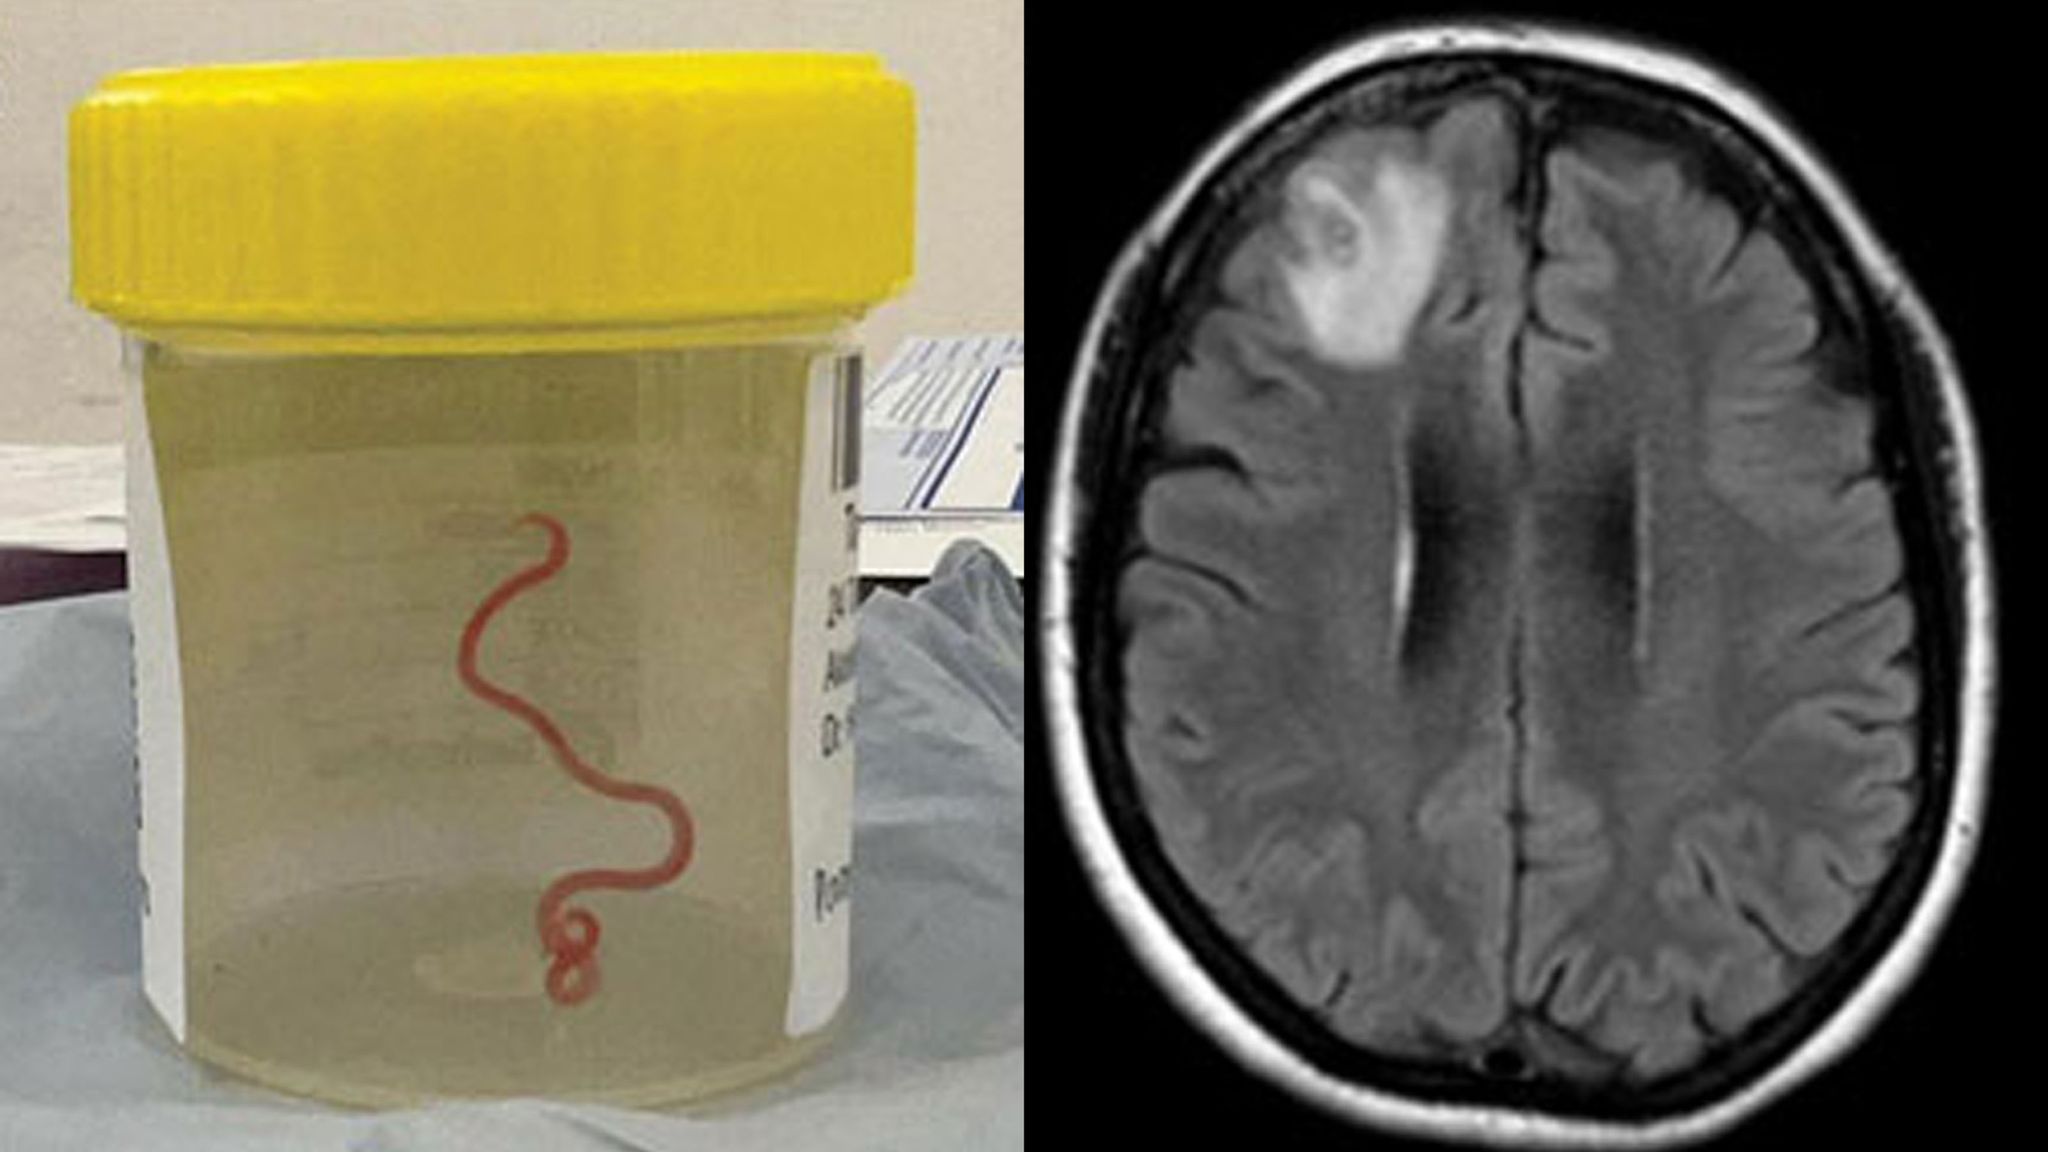

Asaj i është hequr një krimb parazitar 8 cm i gjatë.

UBT newsNjë gruaje që po përjetonte harresë dhe depresion i është hequr një krimb parazitar 8 cm i gjatë nga truri i saj.

Një skanim MRI i trurit të saj zbuloi se një helminth i lëvizshëm – krimb parazitar – jetonte në lezionin e lobit frontal të djathtë të trurit të saj.

Ndërhyrja kirurgjikale u bë alternativa e vetme dhe mjekët hoqën me sukses krimbin, i cili ishte 8 cm në gjatësi dhe 1 mm në diametër.

Rasti është i paprecedentë në historinë mjekësore dhe është dokumentuar në revistën e Sëmundjeve Infektive në zhvillim.